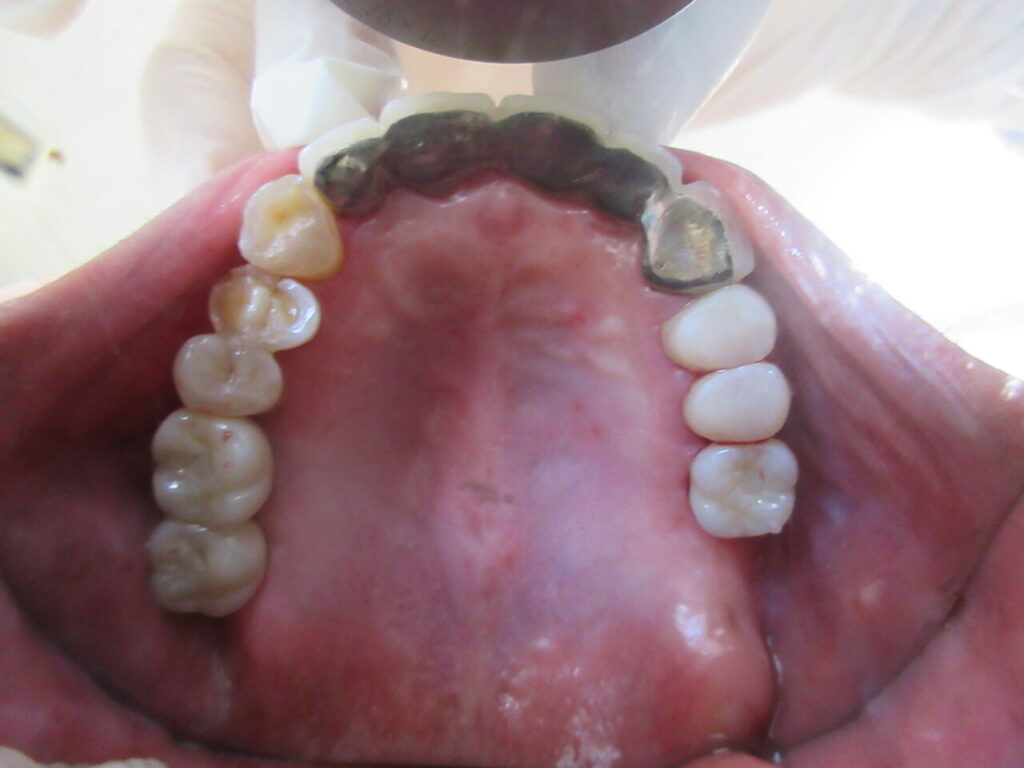

今日は上顎両側のインプラントの上部構造をセット。